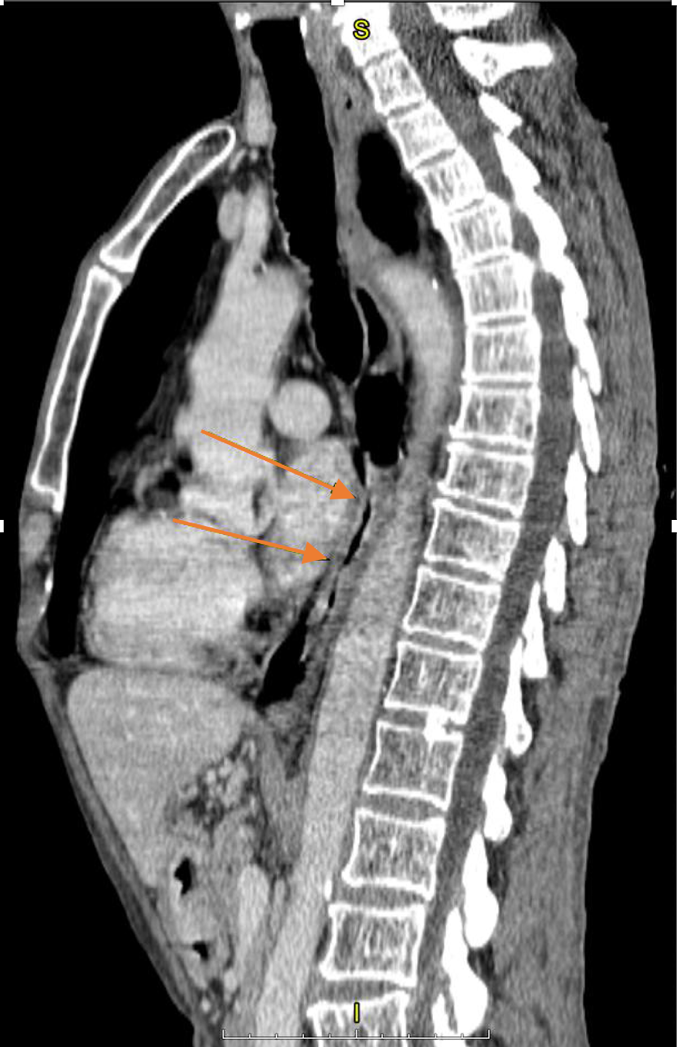

Материал и методы. Представлено 3 клинических случая одновременного развития плоскоклеточного рака пищевода и аденокарциномы желудка у пациентов, получавших лечение в ГУЗ «Областной клинический онкологический диспансер», г. Ульяновск, и ГАУЗ СО «Свердловский областной онкологический диспансер», г. Екатеринбург. Пациентам проведены хирургическое вмешательство, химиотерапия и лучевая терапия.

Результаты. Первично-множественный синхронный плоскоклеточный рак пищевода и аденокарцинома желудка представляют собой сложную клиническую задачу, требующую вмешательства мультидисциплинарной команды специалистов. Химиолучевая терапия с использованием схемы FOLFOX продемонстрировала хорошую переносимость и позволила достичь удовлетворительного клинического ответа со стороны опухолей обеих локализаций.